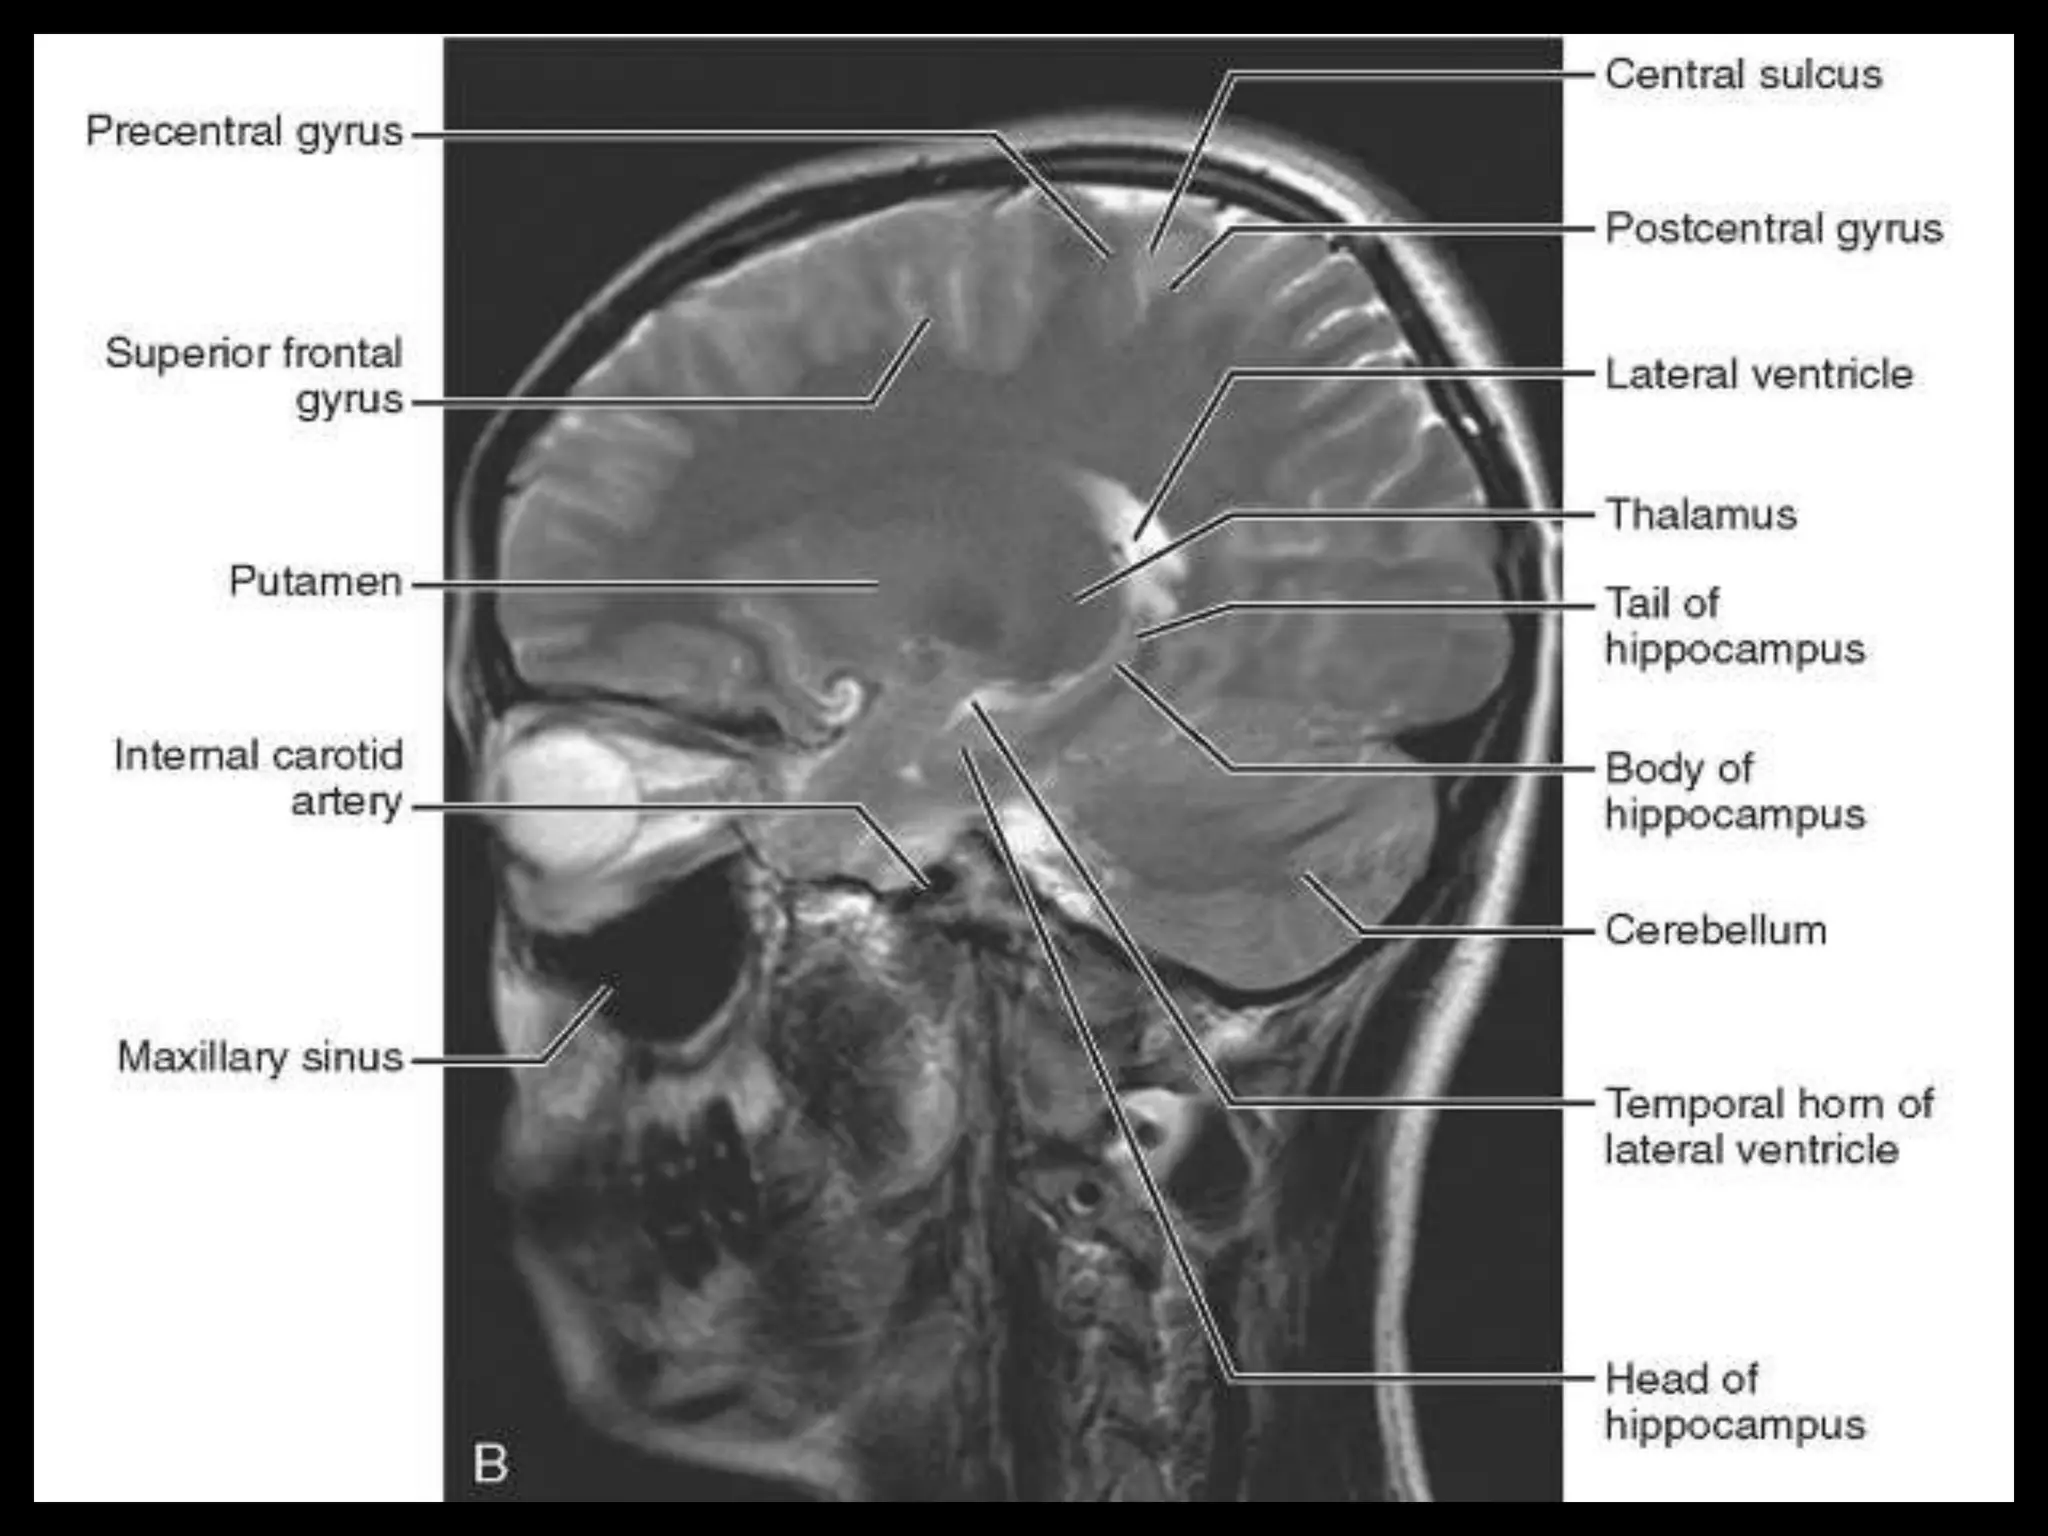

The two cerebralhemispheres are separated by interhemispheric fissures and falx cerebri. On the lateral surface of the brain, the sylvian fissure (lateral fissure) and the rolandic fissure (central fissure) separate the cerebral hemisphere into the frontal lobe, temporal lobe, parietal lobe, and a line drawn from the parieto-occipital sulcus onto the preoccipital notch, delineating the boundaries of the parietal and temporal lobes from that of the occipital lobe. The frontal lobe, the largest of all the brain, has four principal gyri: the precentral gyrus and the superior frontal, middle frontal, and inferior frontal gyri. The precentral gyrus, parallel to the central sulcus, together with the anterior bank of the central sulcus, comprises the primary motor area, which is one of the most important cortical areas for movement. Rostral to the precentral sulcus is the premotor area, another important area for movement. The middle frontal gyrus contains Brodmann’s area 8, known as the frontal eye field, which is important for conjugate eye movements. Another important motor area for speech called Broca’s area, is located at the triangular and the opercular parts of the inferior frontal gyrus in the dominant hemisphere.

In the parietallobe, there are a postcentral gyrus, a superior parietal lobule, and an inferior parietal lobule. The postcentral gyrus is a primary somesthetic area involved in general body sensation. In the temporal lobe, the superior, middle, and inferior temporal gyri are separated by the two transverse sulci. The posterior fossa contains the cerebellum and brain stem. The posterior fossa is outlined by the clivus and petrous bones anteroinferiorly, the tentorium cerebelli superiorly, and the occipital bone posteroinferiorly. The cerebellum is located posteriorly in the two thirds of the posterior fossa, separated from the brain stem by the fourth ventricle. The brain stem occupies the anterior third of the posterior fossa, including the midbrain, pons, and medulla oblongata. The brain derives its vascular supply via two carotid and two vertebral arteries. The internal carotid artery bifurcates terminally into the anterior and middle cerebral arteries. The two vertebral arteries unite at the caudal border of the pons to form the basilar artery.

Sectional Anatomy: NormalAxial CT and MRI Anatomy. On CT and MR scans, the brain has been briefly viewed in infratentorial and supratentorial sections, as described below. CT scans are performed with a 15- to 20-degree angulation to the canthomeatal line at 8-mm increments. MRI scans are generally obtained parallel to the AC-PC line in the axial plane with 6-mm slice thickness. Using the sagittal view, the coronal sections are acquired parallel to the brain stem, and the sagittal sections are obtained perpendicular to the axial section. On MRI studies, cranial nerves IX and X can be demonstrated at this level because they emerge from the postolivary sulcus. The posterior aspect of the cerebellar hemispheres is outlined by the inferior portion of the cisterna magna.